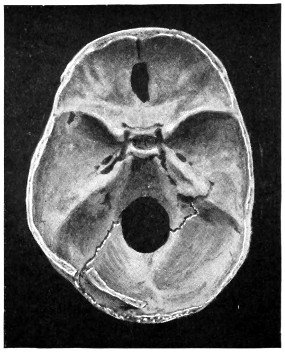

29 A and B. The base of the skull and the base as seen on transillumination 70, 71

30. Plan of the base of the skull 77

50 A and B. The inner aspect of the skull and the same seen on transillumination 137